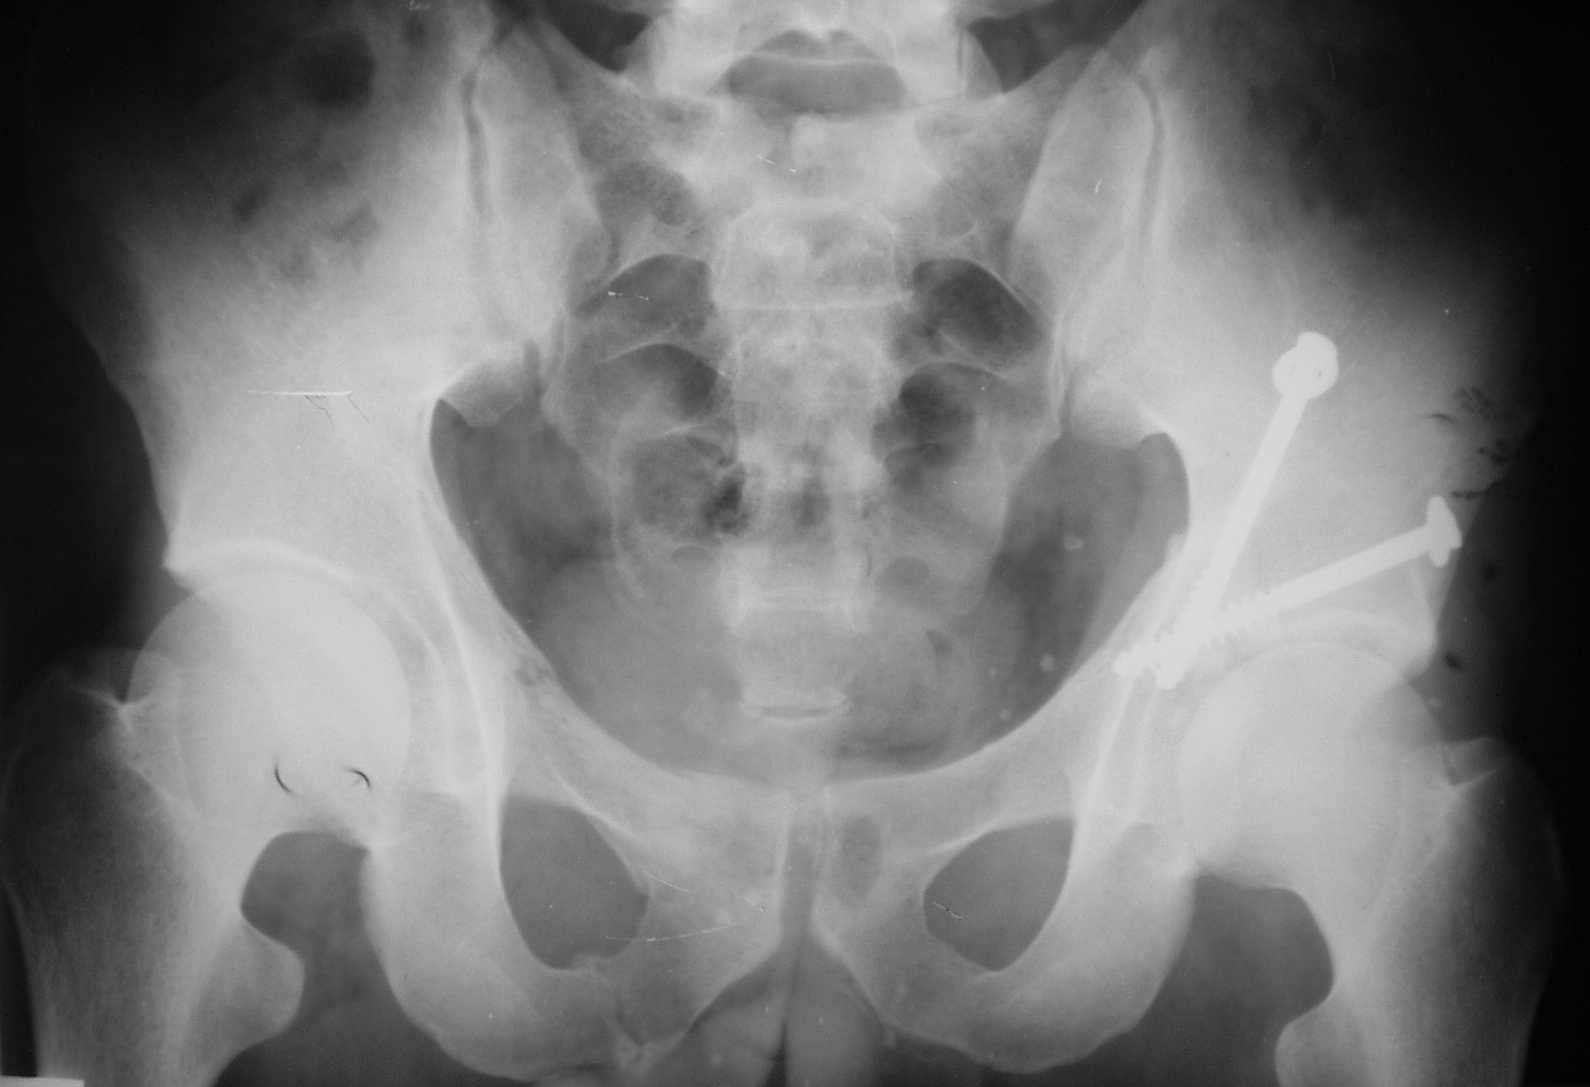

[Ortho] Acetabulum fracture

Dear dr Yordan !  I would do internal fixation as soon as possible. I sent to you one of my case with using of anterior iliofemoral approach - 5-th day after the accident. Best regards. Anatoliy Kanzyuba, MD. Donetsk Ukraine

Имя     : 1.JPG

Размер  : 64911 байтов